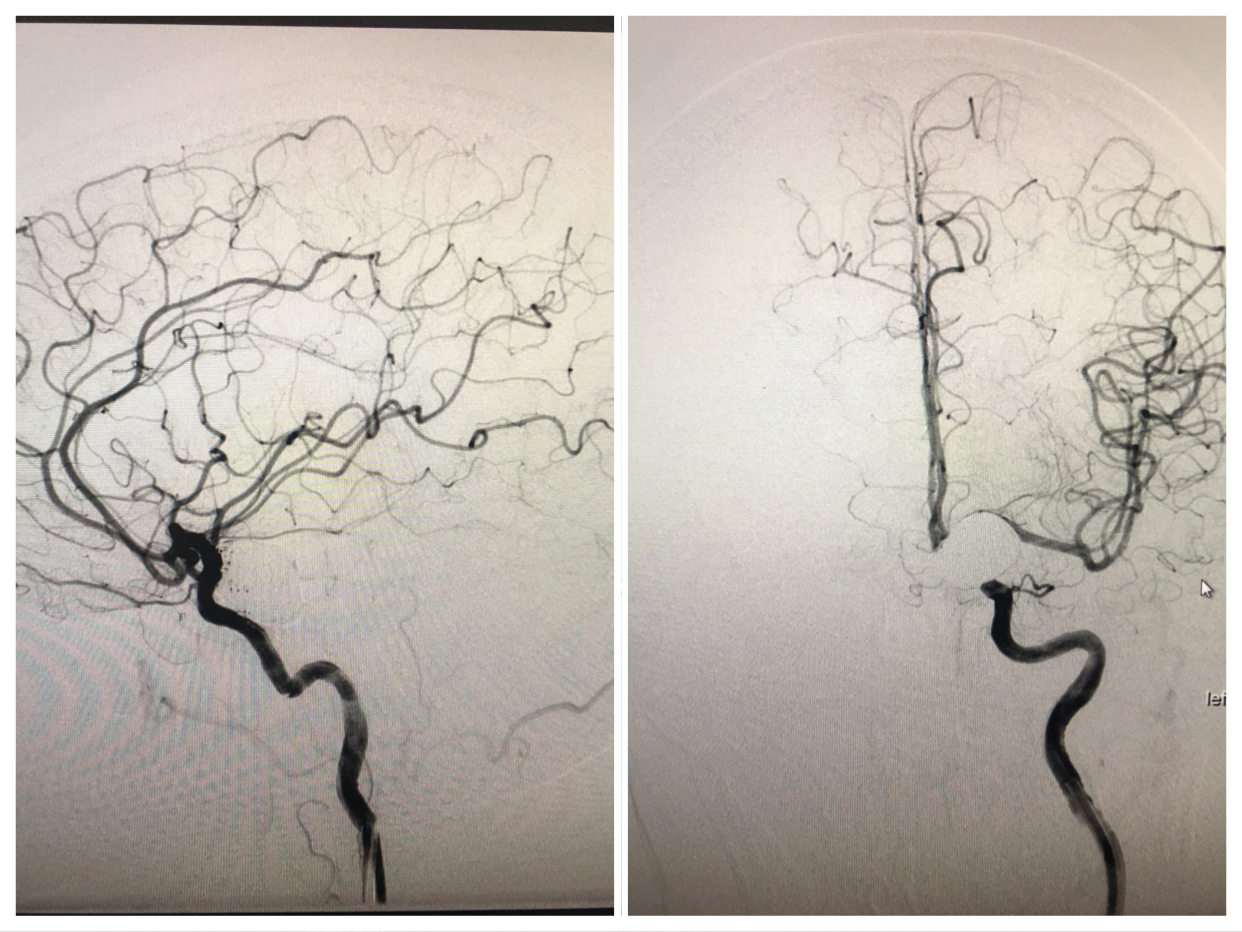

經(jīng)科室會診、與家屬充分溝通,在上級專家指導下行顱內(nèi)動脈瘤彈簧圈栓塞+支架植入術,術中支架釋放順利。術畢造影:瘤腔栓塞致密,瘤頸未見殘留,支架貼壁良好,各級血管分支分布未見缺失,供血良好,手術順利完美結束。目前患者已康復出院。